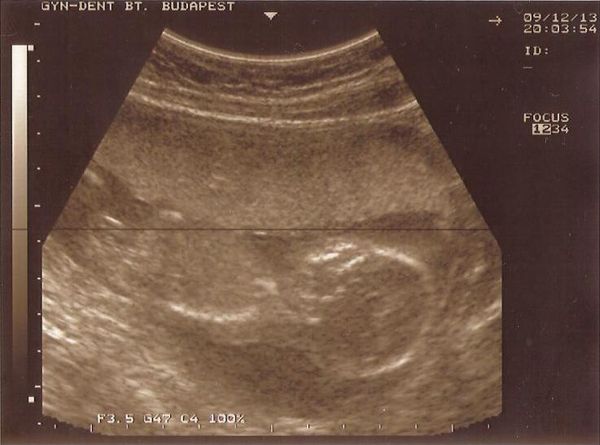

? Kb. 1 hete folyamatosan fáj a hasam, de hát múlt kedden voltunk UH-n, így azzal nyugtatom magam, hogy nagy baj nem lehet. Péntek este meg úgyis megyünk a genetikai UH-ra, addig meg csak kibírom, és remélem nem jön vissza az erősebb fájdalom. Ott meg megkérdezem majd a dokit, mit mond erre.